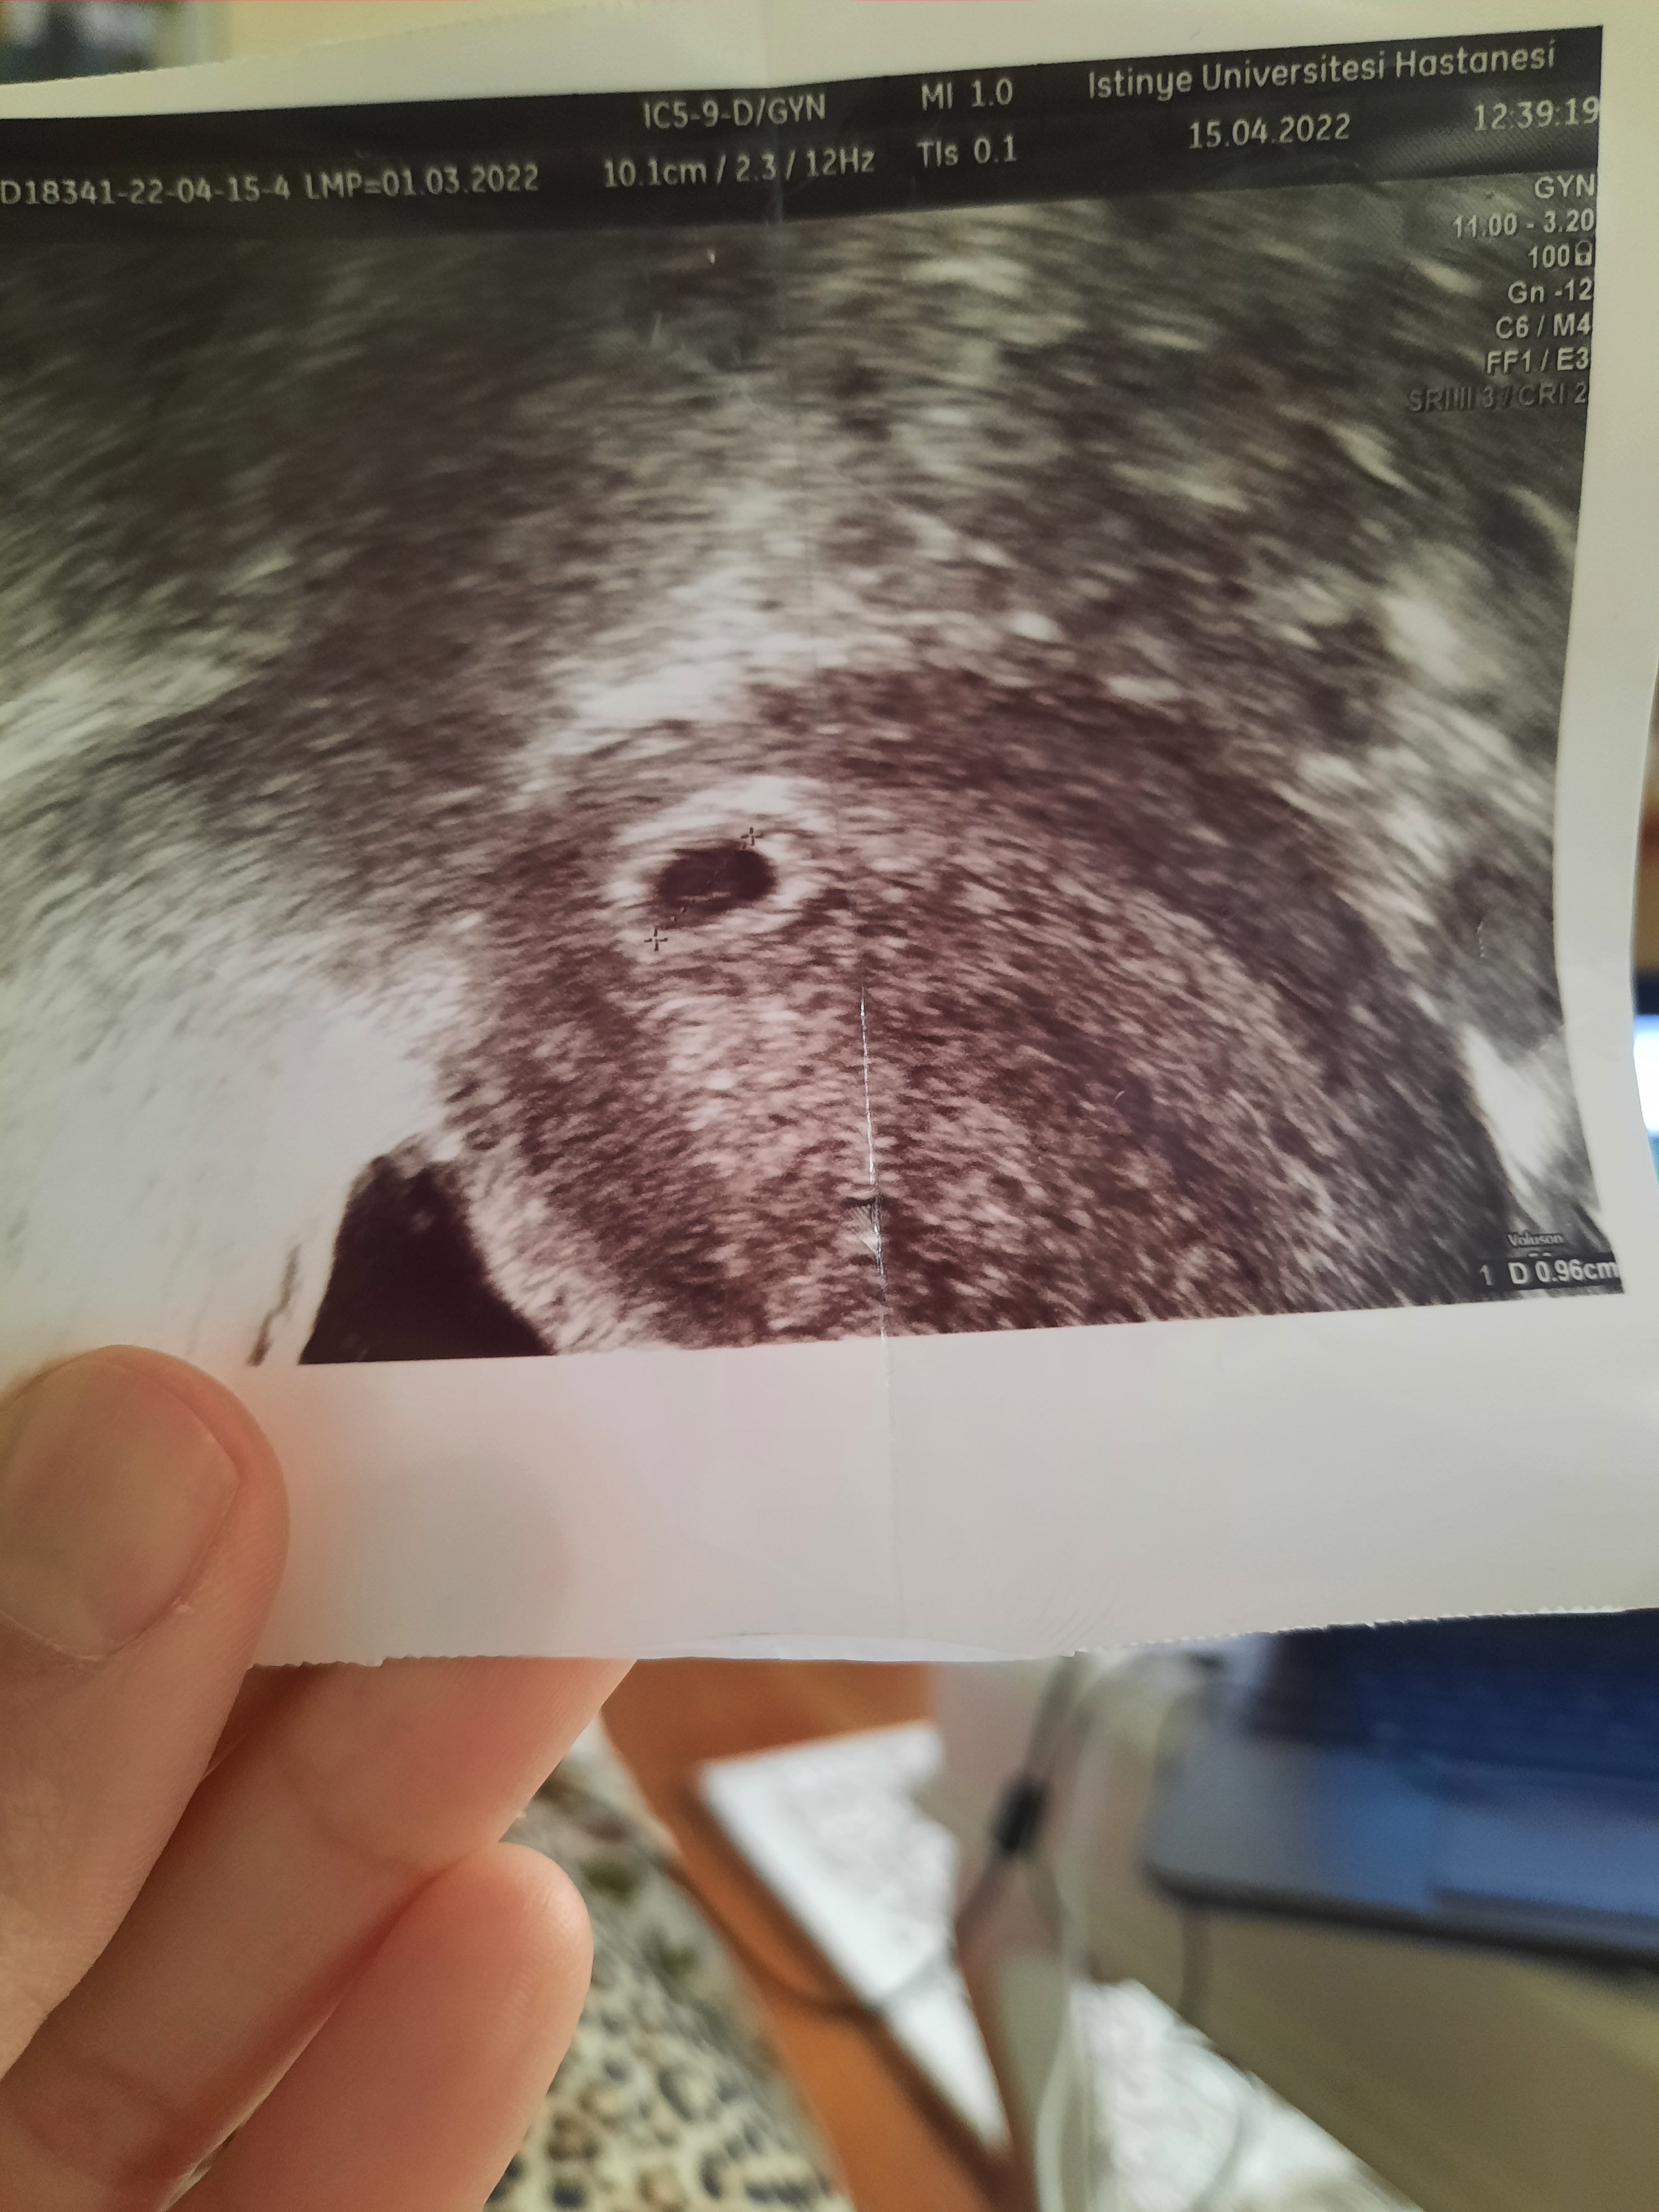

Canım attım bakarsın ilk attığım 1 inci keseyi görmeye gittiğimde hersey güzeldi ama kesenin altında kese gibi bisey vardı ondada kan vardı o bozabilir sürekli dinlen yat dedi kanama tehliken var dedi ama 2inci si 1 inci olan gibi kalmış buyur mu umutlaniyorum ama okuduklarımi görünce umudum da kalmıyor rabbim bilir dedim

• 20220416_181600.jpg

20220416_181600.jpg

1,018.9 KB · Görüntüleme: 173